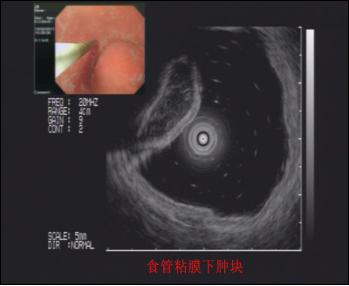

9. 超声内镜介(EUS)入技术 如EUS引导下细针穿刺细胞学检查及注射、引流等。

超声内镜技术